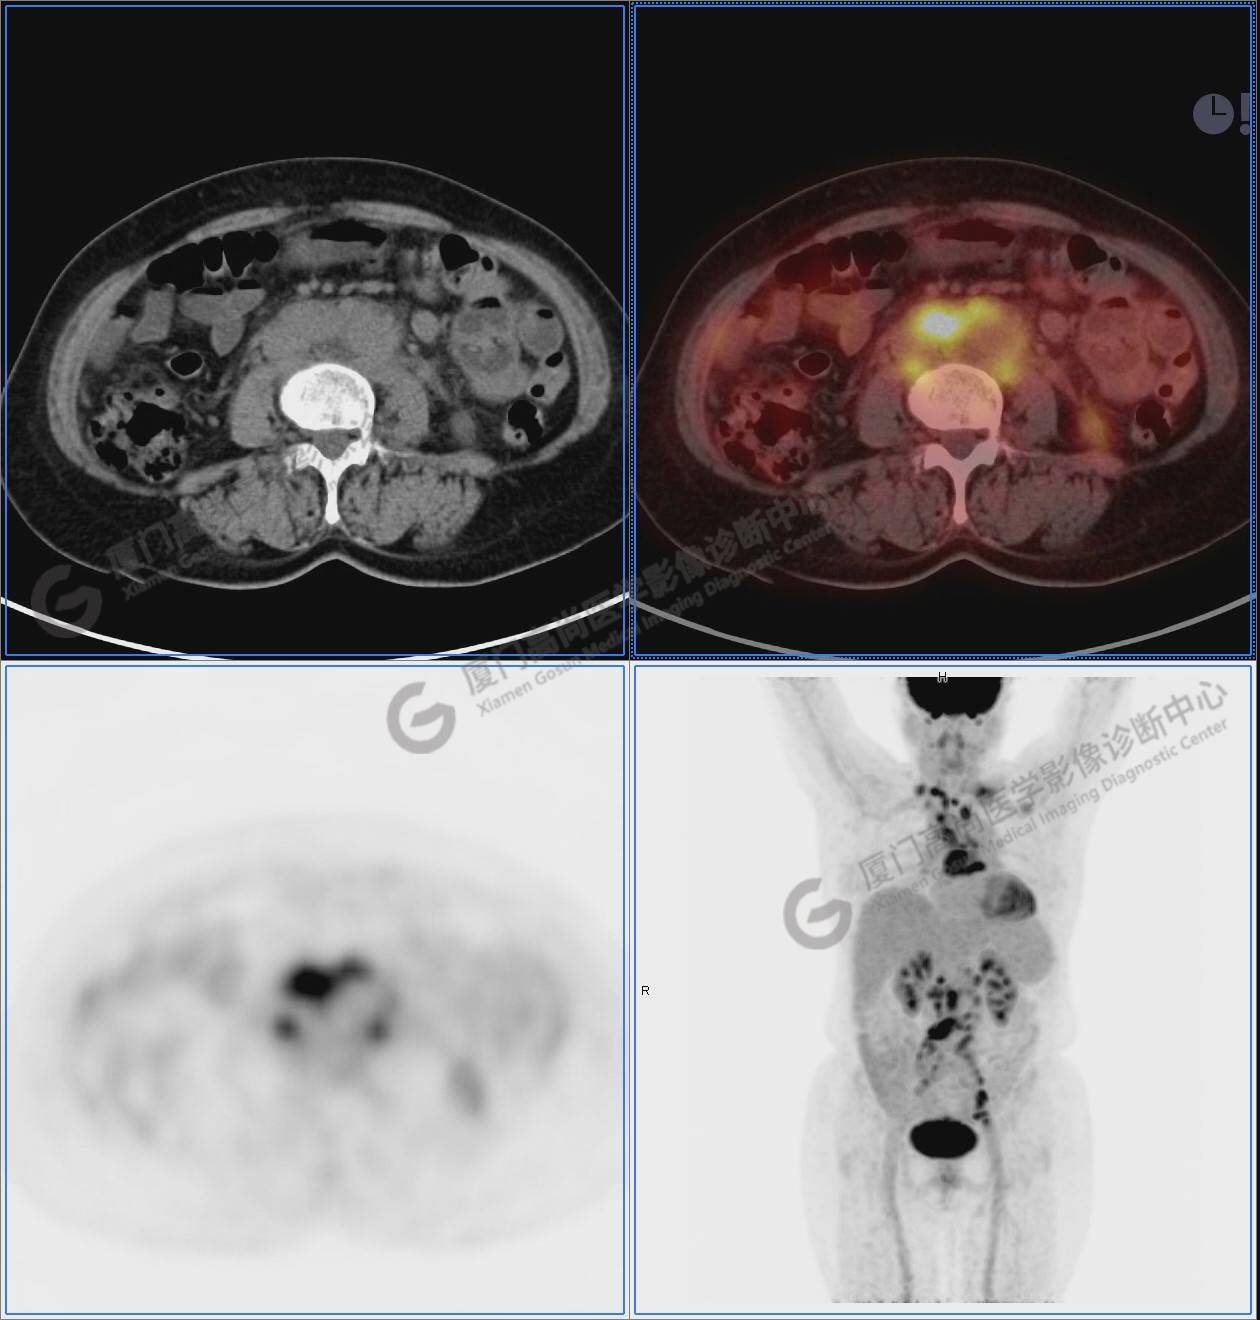

圖2-9:雙側(cè)鎖骨區(qū)、縱隔、右側(cè)內(nèi)乳區(qū)、腸系膜緣、腹膜后、雙側(cè)髂血管旁及盆腔多發(fā)腫大淋巴結(jié)影,代謝不同程度增高,考慮為轉(zhuǎn)移。

圖6

圖7

圖8

圖9